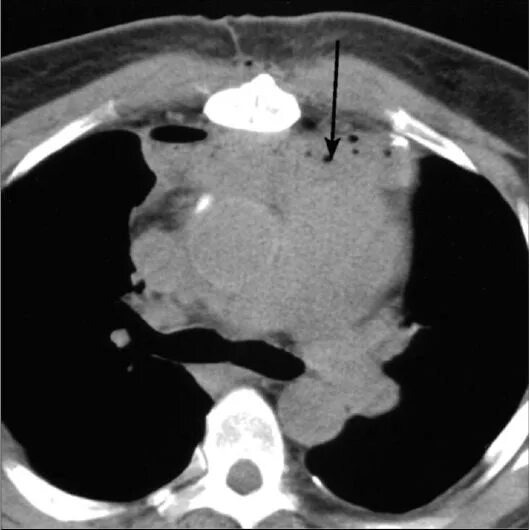

На представленном ниже примере в переднем отделе верхнего этажа средостения определяется воспалительный инфильтрат жидкостной структуры с наличием пузырьков воздуха (от деятельности бактерий), распространяющийся кверху до клетчаточного пространства шеи.

Инфильтрат определяется кпереди от аорты и лёгочного ствола на уровне бифуркации трахеи. КТ ОГК, средостенное окно, натив

Другой пациент с медиастинитом на фоне флегмоны шеи.

В процесс вовлечен перикард. Двусторонний гидроторакс с компрессионным ателектазом левого лёгкого.